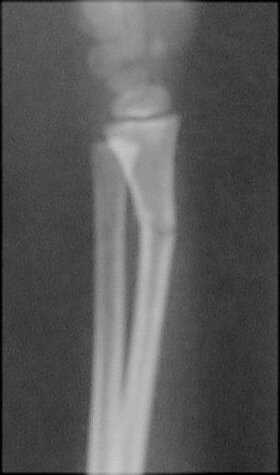

Return to Greenstick Fracture